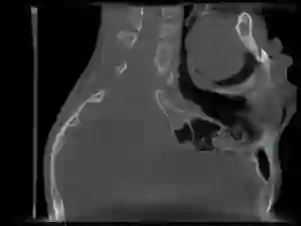

Detecting 3D landmarks on cone-beam computed tomography (CBCT) is crucial to assessing and quantifying the anatomical abnormalities in 3D cephalometric analysis. However, the current methods are time-consuming and suffer from large biases in landmark localization, leading to unreliable diagnosis results. In this work, we propose a novel Structure-Aware Long Short-Term Memory framework (SA-LSTM) for efficient and accurate 3D landmark detection. To reduce the computational burden, SA-LSTM is designed in two stages. It first locates the coarse landmarks via heatmap regression on a down-sampled CBCT volume and then progressively refines landmarks by attentive offset regression using high-resolution cropped patches. To boost accuracy, SA-LSTM captures global-local dependence among the cropping patches via self-attention. Specifically, a graph attention module implicitly encodes the landmark's global structure to rationalize the predicted position. Furthermore, a novel attention-gated module recursively filters irrelevant local features and maintains high-confident local predictions for aggregating the final result. Experiments show that our method significantly outperforms state-of-the-art methods in terms of efficiency and accuracy on an in-house dataset and a public dataset, achieving 1.64 mm and 2.37 mm average errors, respectively, and using only 0.5 seconds for inferring the whole CBCT volume of resolution 768*768*576. Moreover, all predicted landmarks are within 8 mm error, which is vital for acceptable cephalometric analysis.